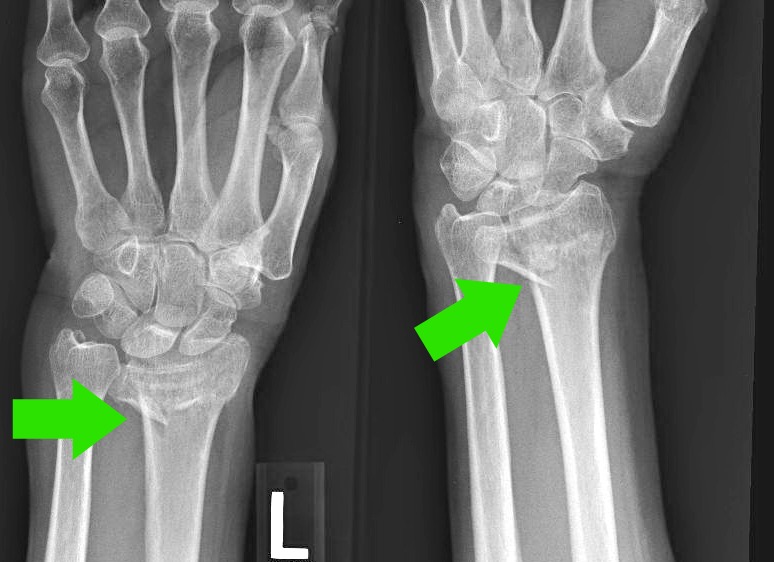

Xray Left wrist joint Fracture with displacement distal end left Radius Break Near Wrist Distal radius fractures are very common. When the radius breaks near the wrist, it is called a distal radius fracture. The break usually happens due to falling on an outstretched or flexed hand. Distal radius fractures are the most. This type of fracture is quite common and can vary in severity, ranging from a minor crack or break to a.. Radius Break Near Wrist.